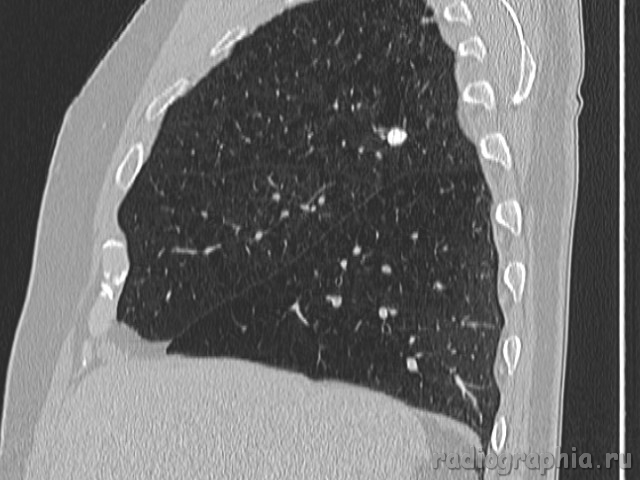

Одиночный узел правого лёгкого.

На рутинном снимке ОГК, был выявлен одиночный узел; по протоколу выполнили КТ. Какое было бы ваше заключение; и как бы Вы поступили если у вас нет возможности выполнять КТ?